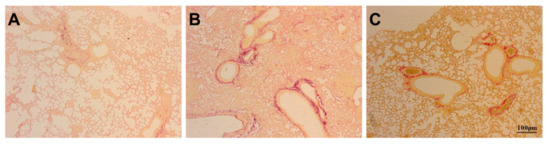

3.3. Assessment of Pulmonary Fibrosis